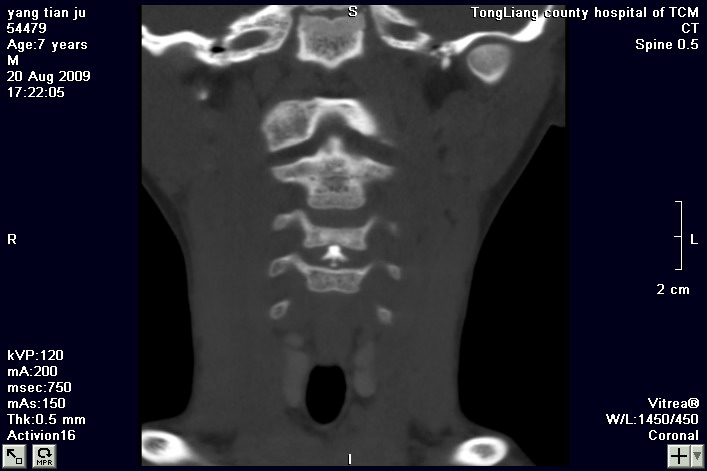

标题: PED2853:颈3/4椎间盘内高密度钙化灶,请各位会诊. [打印本页]

标题: PED2853:颈3/4椎间盘内高密度钙化灶,请各位会诊.

患儿,7岁,颈部疼痛3天,颈部活动受限.

本例应该是典型的儿童钙化性椎间盘病。

儿童钙化性椎间盘病发病年龄多在5~12岁,男女比例相当,大多数患儿发病主要表现为颈部疼痛,伴活动受限。少数有吞咽不适或肢体瘫痪。有一部分患儿无症状,是在其它检查时发现。病因尚不完全明了,可能的有:1、感染。2外伤。

儿童颈椎椎间盘钙化系一良性自限性疾病,可见于颈、胸、腰椎,以颈椎为多发,腰椎少见,多为单发。钙化位于髓核,也可累及软骨板和纤维环引起钙化主要发生于c 4~7  的髓核位于椎间隙正中或偏后,少数向前疝出,以后部多见,呈梭状、盘状、团块状或半环状;(2)颈椎生理曲度变直,椎间隙正常或增宽;(3)相邻椎体可变扁,局部凹陷变形,椎体前下缘鸟嘴状增生,或呈钳口状改变,椎前软组织增厚及环枢椎半脱位;(4)ct可清晰显示椎间盘髓核 位置的钙化灶及经破裂的纤维环向椎管内突出。(5)mri,钙化在t1及t2加权像上均呈低信号,并可见脊髓组织内异常信号。